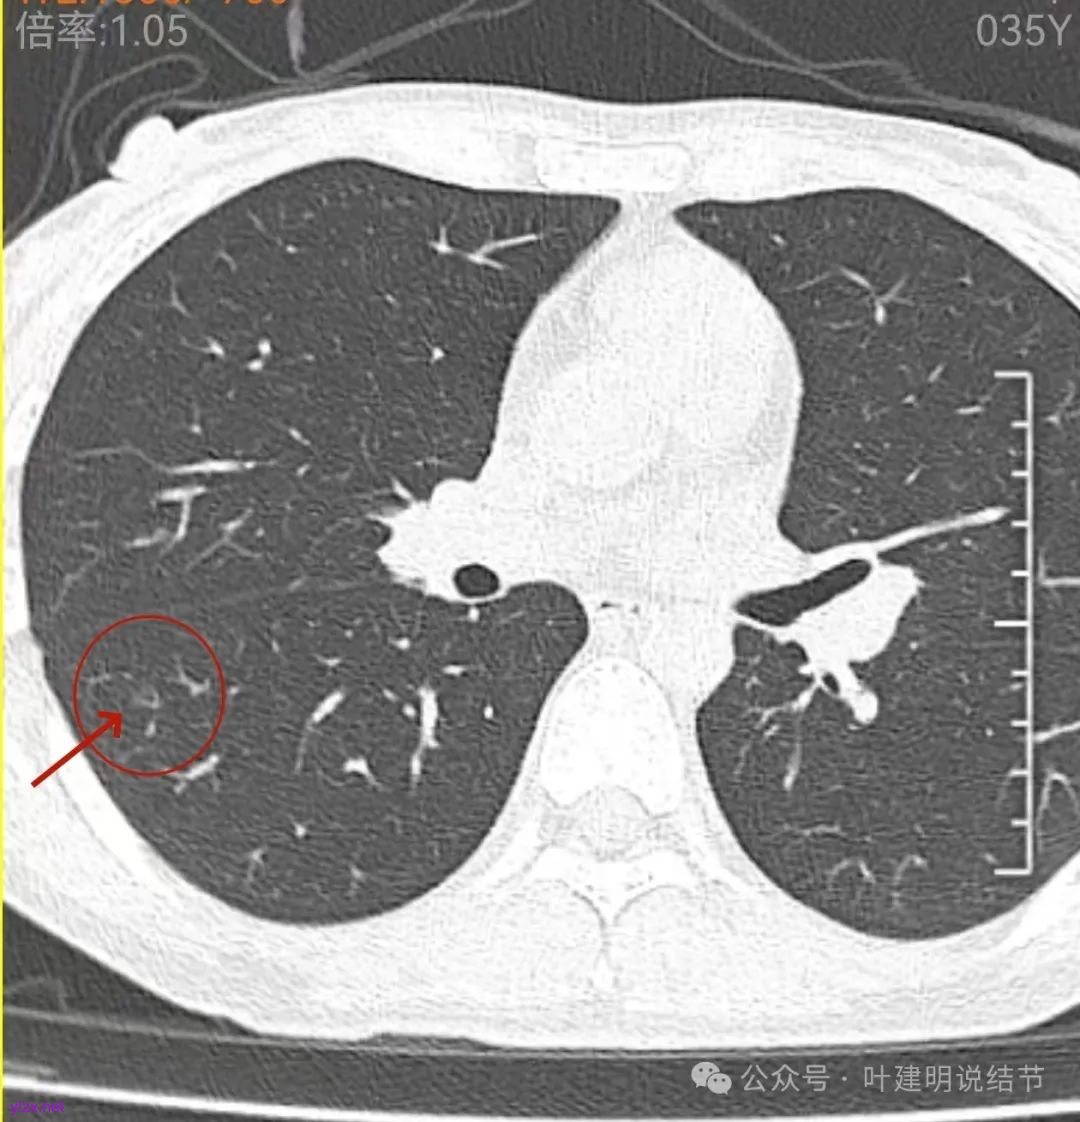

再看2022年9月的影像:

左肺尖病灶当时也有,没有明显变化。

左上叶此处当时也有,只是没有2024年轮廓与边界那么清楚,而且范围也是当时小点的。

右下当时是很淡的,也显偏模糊的磨玻璃影。

怎么有个点状密度较高的结节在?与上面那截图的淡磨并不完全在一块的。